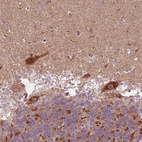

Immunohistochemical staining of human duodenum shows strong granular cytoplasmic positivity in glandular cells.